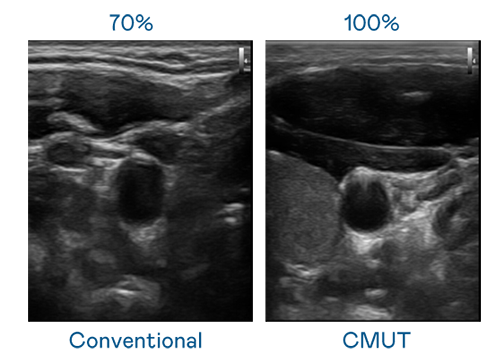

CMUT 技术是一种用电容式微机电元件来产生超音波讯号的技术。与传统 PZT 压电式技术相比,CMUT 频宽增加 30%,更宽频的超音波讯号让影像解析度大幅提升,是实现高影像品质医疗超音波扫描、促进精准医疗发展的关键技术。

大频宽带来超清晰影像

超音波影像的解析度高低,首先取决于探头能发出的讯号频宽。stake CMUT 可提供高清晰的超音波讯号,提供高频宽、高灵敏度、影像纹理细节更高的超音波影像,协助医护人员缩短影像判读时间及利用精准的医疗影像进行诊断。